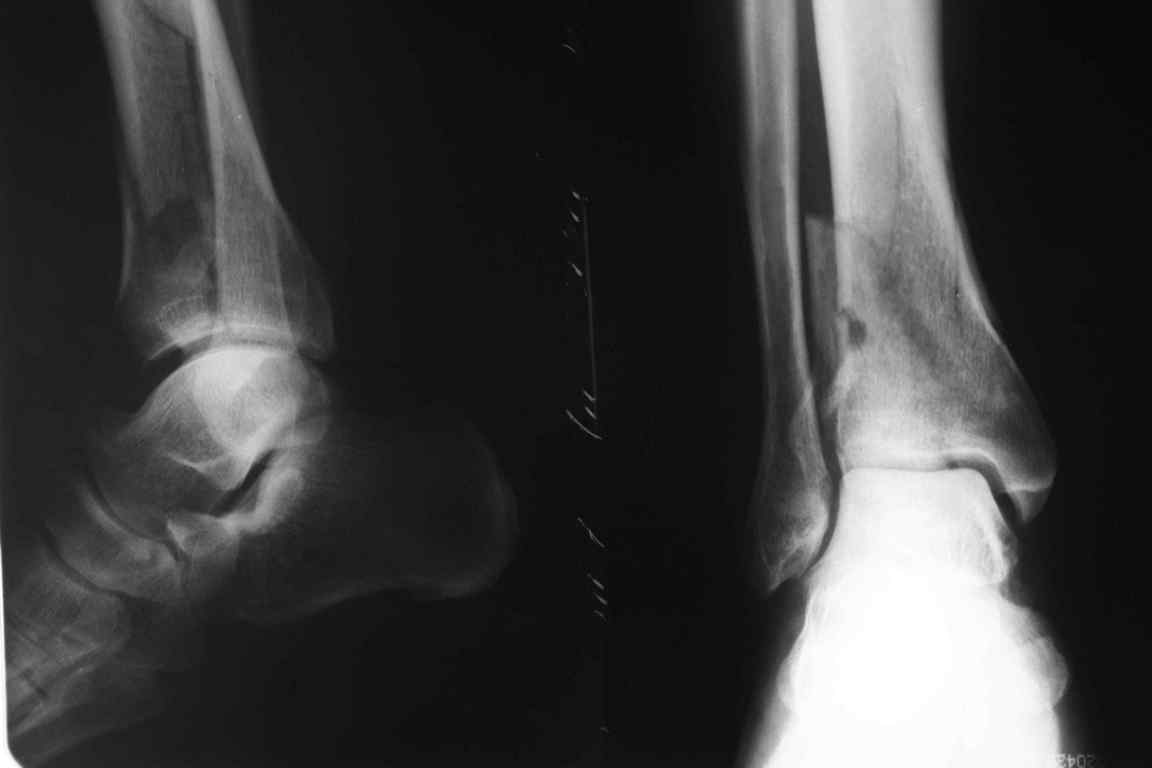

Уважаемый коллега! Обычно, хирургичское лечение переломов пилона начинают с остеосинтеза малоберцовой кости (чего не продемонстрировали коллеги из Новокузнецка). В Вашем случае нет убедительных данных за перелом малоберцовой кости, так что, видимо, этот этап вы пропускаете. После чего переходят собственно к пилону - основные усилия в лечении которого необходимо направить на устранение импрессии (отчетливо видна на боковой R-грамме), затем пластика дефекта ну и накостный остеоинтез платиной, коих достаточно много. Хотел бы предостеречь Вас от: закрытой "малоинвазивной" техники в данном случае, так как для устранения импрессии малоинвазивно необходим определенный опыт и начинать с этого я бы не стал, использовать пластину Pilon Plate-имплант сложный в установке и , опять же, требует определенных навыков. Я бы синтезировал традиционной пластиной "лист клевера" с угловой стабильностью.

Есть смысл начать с наложения дистрактора голень-стопа. Лигаментотаксис может очень существенно помочь с репозицией. При переломе малоберцовой кости этот подход позволяет не тратить время на ее остеосинтез. Больших участков импрессии суставной поверхности не видно, перелом больше по типу раскалывания. Это делает возможной полностью закрытую репозицию с фиксацией либо аппаратом, либо компрессирующими винтами и аппаратом, либо пластиной малоинвазивно.

1 - перелом закрытый;

2 - соотношение осей голени и стопы практически идеальное;

И какой смысл переводить закрытый в открытый, подвергать операционным рискам пациента с ГБ в 60 лет? Тем более, что после операции наступать на ногу ему никто не разрешит минимум 3 месяца. Моё мнение - только консервативно и под регулярным контролем и дозированным ЛФК, причем движения в суставе начинать не познее конца 6-ой недели, а лучше с 5-ой.

На снимках смещение не является критичным для явного плохого исхода. Видали и больше, и все замечательно при консервативном лечении. (импрессии по моему нет, подвывиха тоже, вылечить рентгенограмму можно - а цена для больного?)